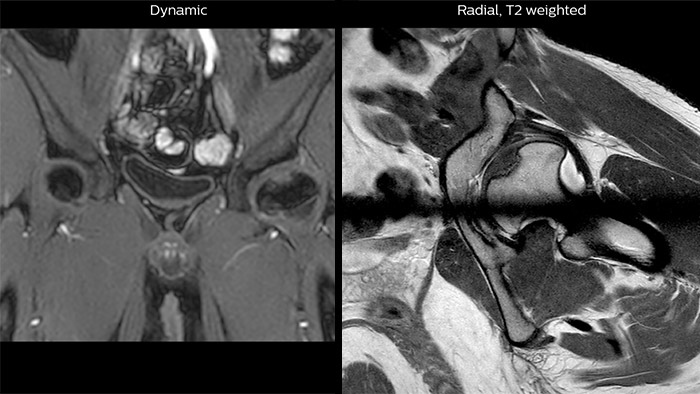

Perthes disease in left hip The affected area on the upper circumference of the left hip shows contrast uptake in the dynamic scan. The radial scan nicely depicts the hip area, despite the dark shape in the center that is inherent to the radial way of scanning.